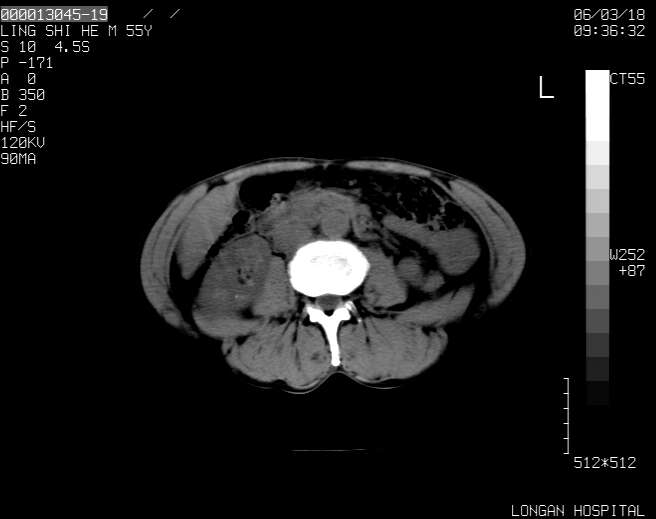

以下是引用guzhongliangddd在2006-3-21 22:13:00的发言:[br]病灶主要位于肝右叶的后份,内见异常血管,门脉主干及右支受侵{提示有癌栓形成},门腔间隙内见增大淋巴结。肝左叶内未见异常。

以下是引用zhuxinli在2006-3-22 1:23:00的发言:[br][br] 病灶主要位于肝右叶的后份,内见异常血管 .门脉右支截断,右叶前段早期强化(考虑动静脉漏),腹膜后肿大淋巴结,病灶逐渐强化,考虑为胆管细胞癌[br]